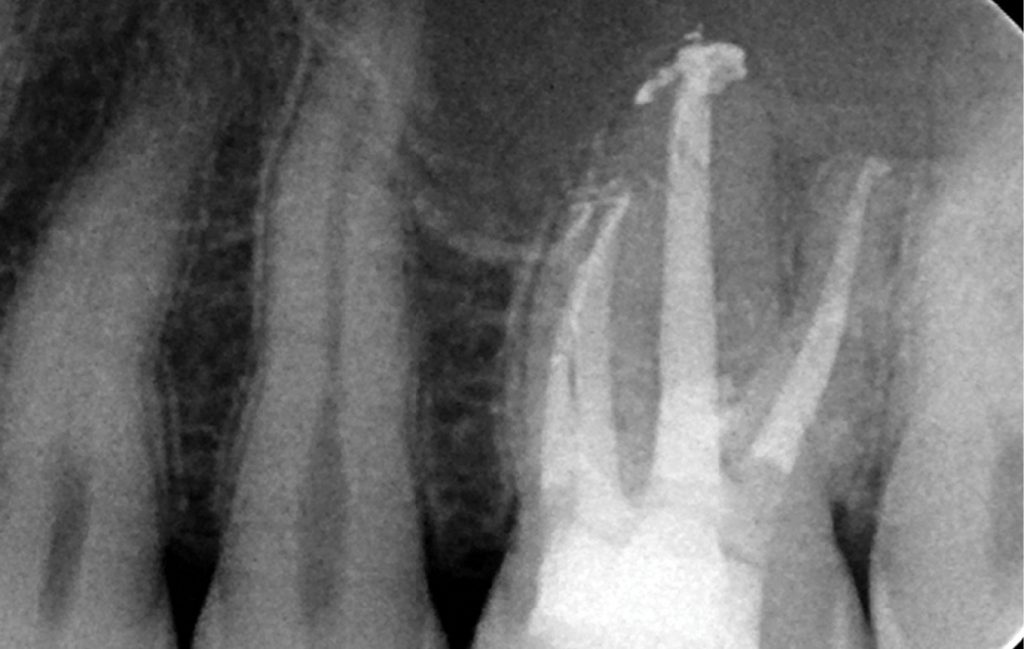

Streszczenie: W pracy przedstawiono krok po kroku proces zaopatrywania perforacji preparatem MTA. Przedstawiono leczenie dwóch przypadków perforacji korzenia oraz jednego przypadku perforacji dna komory.

Summary: The work presents, step by step, the process of sealing perforations with MTA. Two cases of root perforation and one case of chamber floor perforation are presented in the text.

Perforacje ściany korzenia bądź dna komory mogą być wynikiem procesów patologicznych (próchnica, resorpcja) lub mają podłoże jatrogenne, jako powikłanie w leczeniu endodontycznym (szukanie kanałów, udrażnianie zobliterowanych kanałów) lub protetycznym (preparacja pod wkład koronowo-korzeniowy) (1).

Podczas perforacji dochodzi do naruszenia tkanek przyzębia, skutkującej resorpcją kości, tworzeniem tkanki ziarninowej, proliferacji nabłonka, co w późniejszym czasie może prowadzić do powstania patologicznych kieszonek przyzębnych (2).

Niefizjologiczna komunikacja między systemem kanałowym a tkankami otaczającymi ząb lub jamę ustną obniża prognozę dla leczenia kanałowego i może prowadzić do konieczności ekstrakcji zęba. [...]